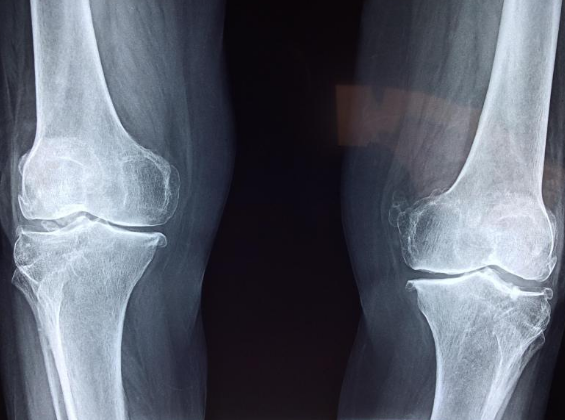

어머니는 수년간 무릎 통증으로 고통을 겪었으며 일반 정형외과 및 한의원에서 다양한 치료를 시도했지만 별다른 효과가 없었고, 연골이 거의 없어 수술 이외에는 다른 해결책이 없다는 진단을 받아 결국 무릎 인공관절 수술을 진행하게 되었습니다.

무릎 인공관절 수술은 약 한 시간에서 한 시간 반정도 소요되며 양측 수술일 경우 1차 수술 후 일주일 뒤에 2차 (다른 쪽) 수술이 진행됩니다. 마취는 하반신 마취를 기본으로 하나 환자의 상태에 따라 전신마취를 할 수도 있습니다. 저희 어머니의 경우 수술 후 이틀정도는 통증이 심하셨다고 합니다.